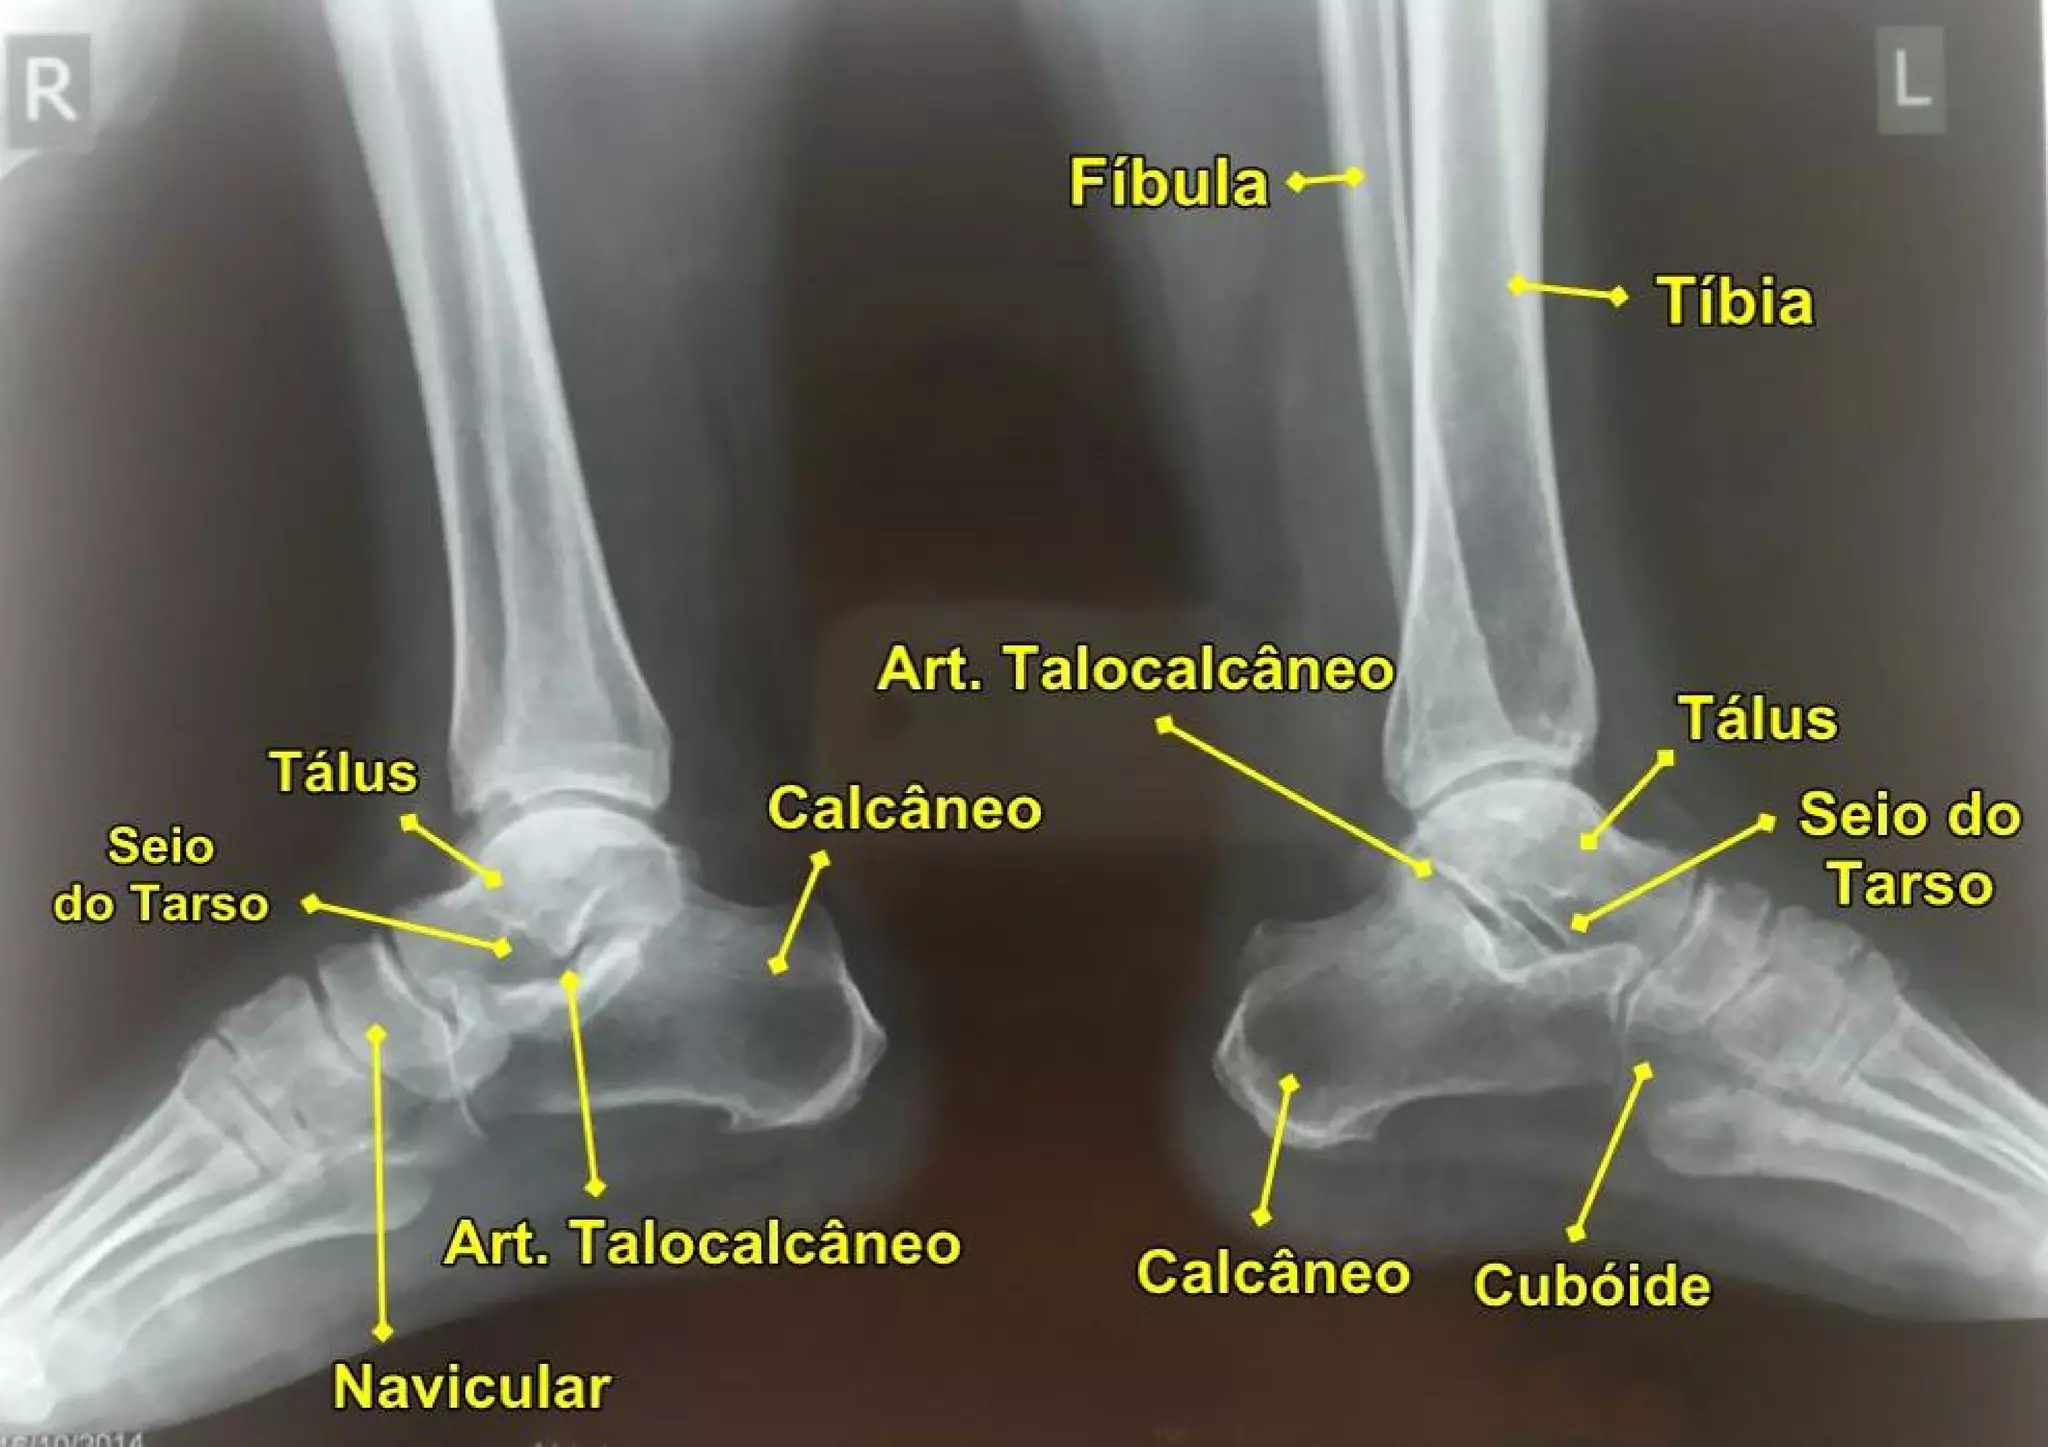

Posicionamento radiológico tornozelo PDF

Anatomia radiológica fixação de contéudo membros inferiores PPT